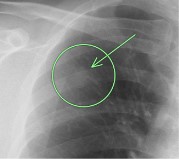

(検診例1)

右肺の真ん中に1cm大の白い結節(○枠)が指摘されました。

胸部CTでは肺に異常はなく、骨島と呼ばれる肋骨の硬化像で(○枠)、全く問題ないものでした。